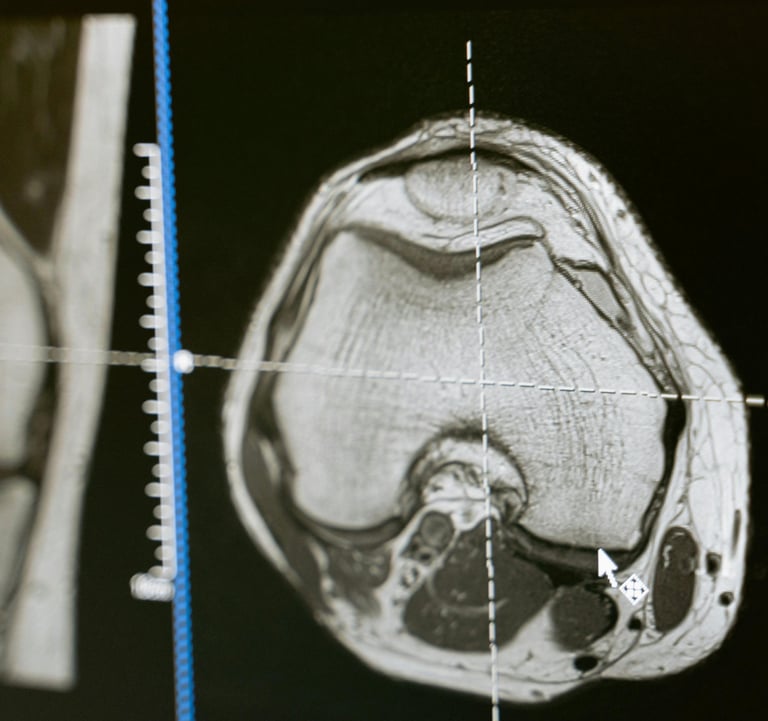

RADIOLOGÍA

El área de radiología, con docentes altamente calificados para brindarte lo mejor en esta nueva era de la inteligencia artificial y cómo cambia todo lo que sabemos del área, además de tener contenido de radiología, también habrá informática. x contenido de radiología para mantenernos actualizados en todo lo relacionado con PACS, HIS, LIS, RIS.